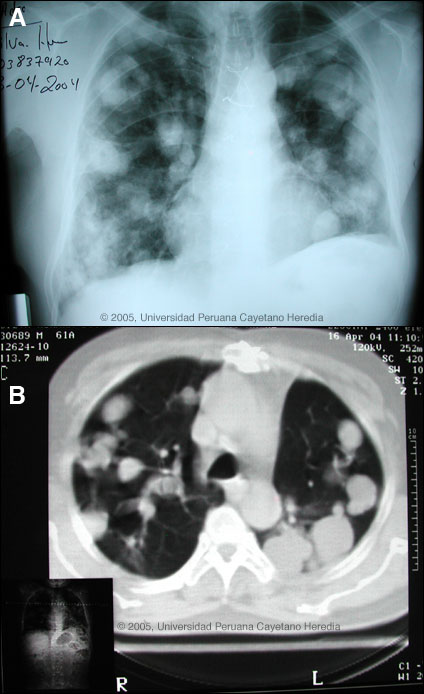

![]() Discussion: ELISA and Western Blot were strongly positive for E. granulosus. Records subsequently obtained indicated that 12 years earlier he had had a spontaneous rupture of a large solitary left-sided pulmonary hydatid cyst. The expectoration of large amounts of clear salty fluid is highly characteristic of this catastrophic event. No medical therapy had been given peri- or post-operatively. Human hydatid disease secondary to Echinococcus granulosus is caused by the larval form of this dog tapeworm. Humans ingest the tapeworm eggs in environments contaminated by canine feces and become accidental intermediate hosts. Sheep are the normal intermediate hosts. Larval cysts expand slowly over years or decades becoming symptomatic as they impinge on other structures by virtue of their size. Spontaneous cyst rupture as occurred here happens in the minority of cases but is not rare. The cysts contain hundreds of viable scoleces capable of becoming adult tapeworms upon ingestion by a definitive host such as the dog. The germinal membrane lining the cyst produces new scoleces on an ongoing basis. Each scolex is capable of becoming a new daughter cyst either within the original cyst or elsewhere should the original cyst rupture or be ruptured. Hydatid disease is common in sheep-raising areas worldwide. Most primary infections involve a single cyst. 65% of solitary cysts are found in liver, 25% in lung and the rest in a wide variety of other organs including kidney, spleen, heart, bone and brain. In patients with a pulmonary cyst, approximately 15% will also have a hepatic cyst. Serology is usually positive with hepatic cysts but sensitivity drops below 50% with solitary pulmonary cysts even when the cyst is large. With the large burden of disease in this patient?s lung a positive serology would be expected. The 2 subsequent chest surgeries in our patient were to resect further cystic hydatid lesions that had developed secondary to seeding of the thoracic cavity during the initial catastrophic event. 7 years prior to presentation to us, the patient received a 1-year course of intermittent albendazole and then 5 years earlier began to receive 6 separate 2-month courses over the following 2 years. At the end of this therapy only a few small residual cysts apparently remained. Praziquantel is the most potent scolicidal drug and is the drug of choice for adult tapeworms. However, praziquantel cannot penetrate the hydatid cyst wall so is only useful as an acute therapy when a cyst ruptures (spontaneously or due to surgical mishap) and scoleces are lying free before encysting again. Albendazole is the therapy of choice for intact cysts that are not operable, such as when there are multiple or diseminated cysts. A trial of Albendazole may also be considered for solitary cysts that are less than about 10 cm. Response is generally slow and only complete in a minority of cases. Surgical resection is the therapy of choice for large solitary cysts. Our patient was begun on continuous albendazole therapy and a follow-up CXR obtained after 7 months is shown in Image C. The plan is to continue therapy for a minimum of 1 year and perhaps as long as 2 years. Liver function tests remain normal in this patient.